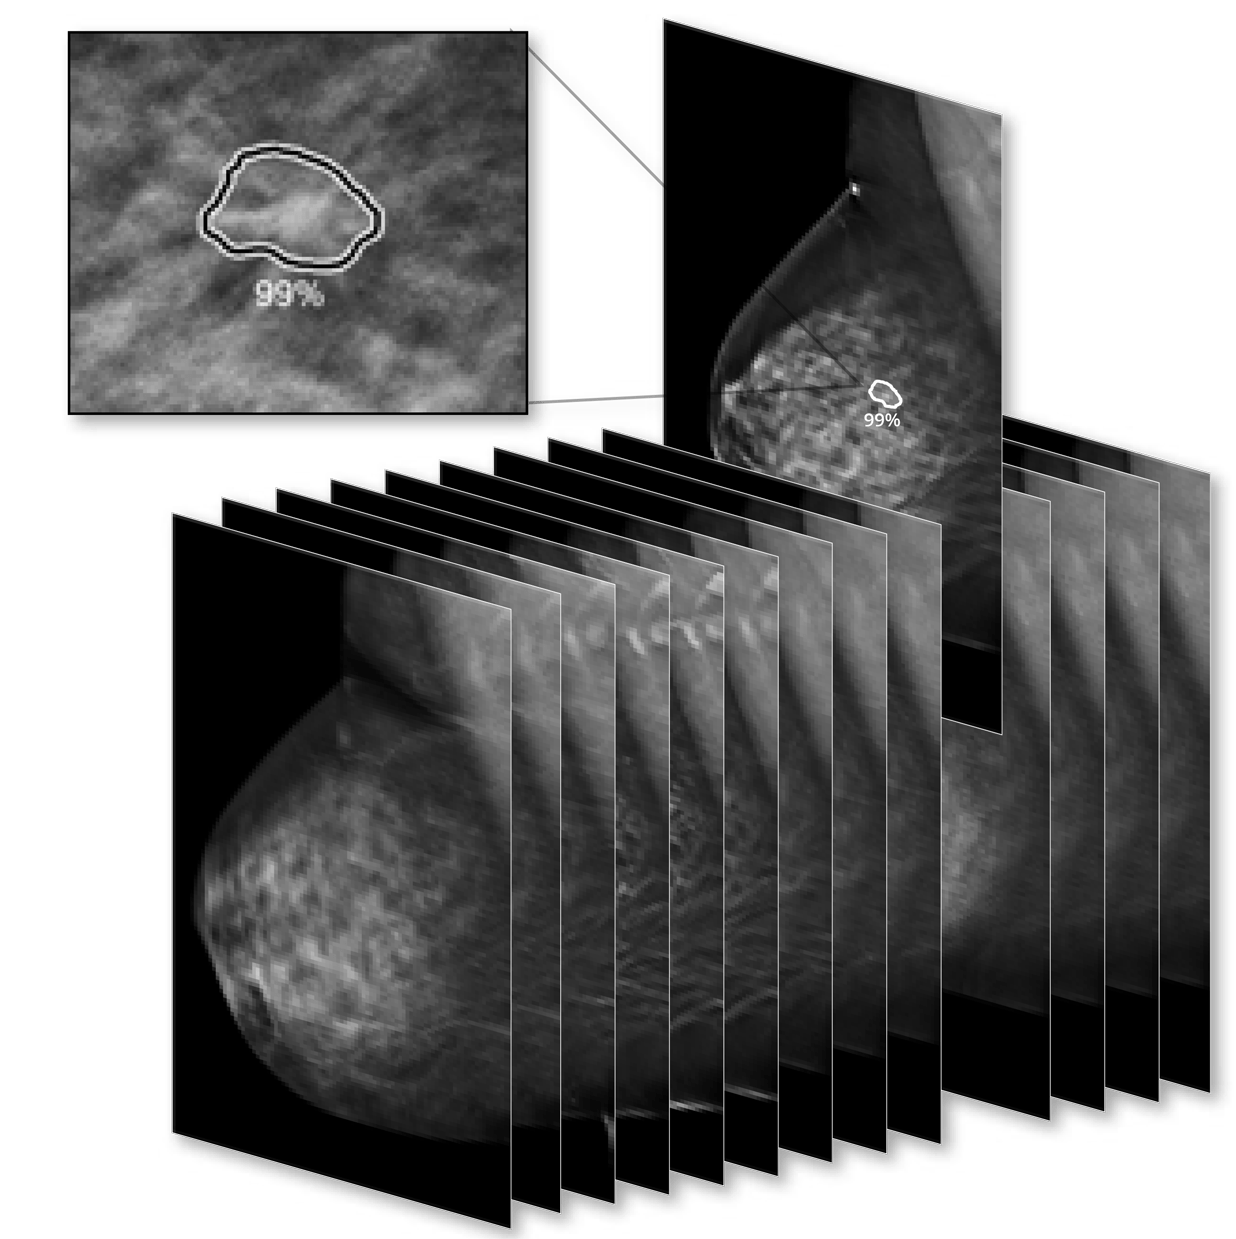

הפתרונות מתבססים על בינה מלאכותית, AI, במטרה להעצים יעילות של זרימת עבודה רוטינית לרדיולוגים בקריאה ממוגרפית ו-DBT , הן במהירות והן באיכות.

התוכנה מזהה צפיפות של הרקמות הרכות, מעריכה את הסיכוי לממאירות, מאתרת קלציפיקציה (calcification) ומבצעת דירוג אוטומטי של המקרה - Case Score.

-2D ProFound AI – בחינה ממוגרפית – CLASS IIA

-3D ProFound AI – בחינת DBT - CLASS IIA